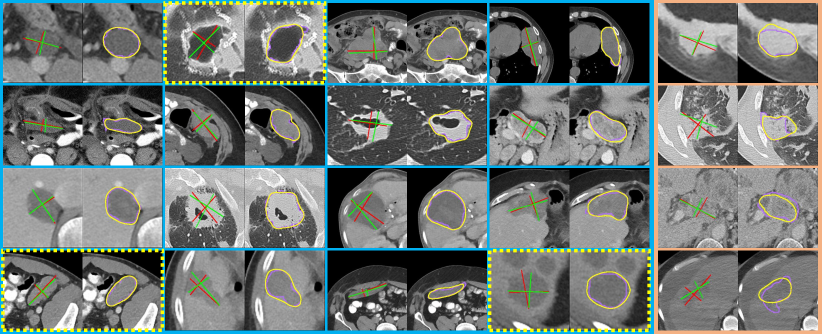

Figure 2: Visual examples of results produced by SEENet. For clear visualization, the lesion segmentation and RECIST estimation results are shown separately. Therefore, each example includes two images. The left one presents the estimated RECIST (the green cross) and the RECIST annotation labeled by radiologists (the red cross). The right one presents the lesion segmentation result (the yellow curve) and the real lesion mask (the pink curve). The yellow dashed boxes indicate some cases where the manual RECISTs are imperfect, but SEENet can fix them (see text). (a) Sixteen good quality examples, (b) two over-estimated (top) and two under-estimated examples (bottom). All images in this figure are cropped from original CT scans according to the results produced by MR-CNN. Best viewed in color.

Qualitative Results. Fig. 2 shows several visual examples of the results produced by SEENet. From Fig. 2, all lesion regions are well cropped, suggesting that SEENet can successfully extract accurate lesion of interests (LOIs) with less human effort (i.e. one manual click) instead of manually drawing bounding boxes to include the lesion regions as done by previous work [2, 17, 18, 1]. Some good quality examples are given in Fig. 2(a), where the automatic lesion segmentation results (the yellow curves) are very close to the manual segmentations (the pink curves) and the estimated RECISTs can well provide the information of lesions’ long and short diameters. As demonstrated by [18], there is a large variation between RECIST annotations from different radiologists. Therefore, it’s easy to understand that the endpoints of the estimated RECISTs are different from the ones of manual annotations. We also find that our estimation results are close to each other even the clicks are given at different positions. Sometimes, although the manual annotations cannot well touch the boundaries of the lesion regions, our estimated results can fix them (seeing the examples indicated with yellow dashed boxes). Two over(under)-estimated results are given in the top (bottom) of Fig. 2(b). In these cases, the boundaries of lesions are highly blurred, which makes SEENet fail to extract highly discriminative features from them to distinguish the lesions from their surrounding regions, especially for lesion segmentation, since only weak pixel-wise labels are used for training. These qualitative results intuitively demonstrate that the proposed framework SEENet can well perform the lesion segmentation and RECIST estimation simultaneously with one-click guide information during inference.